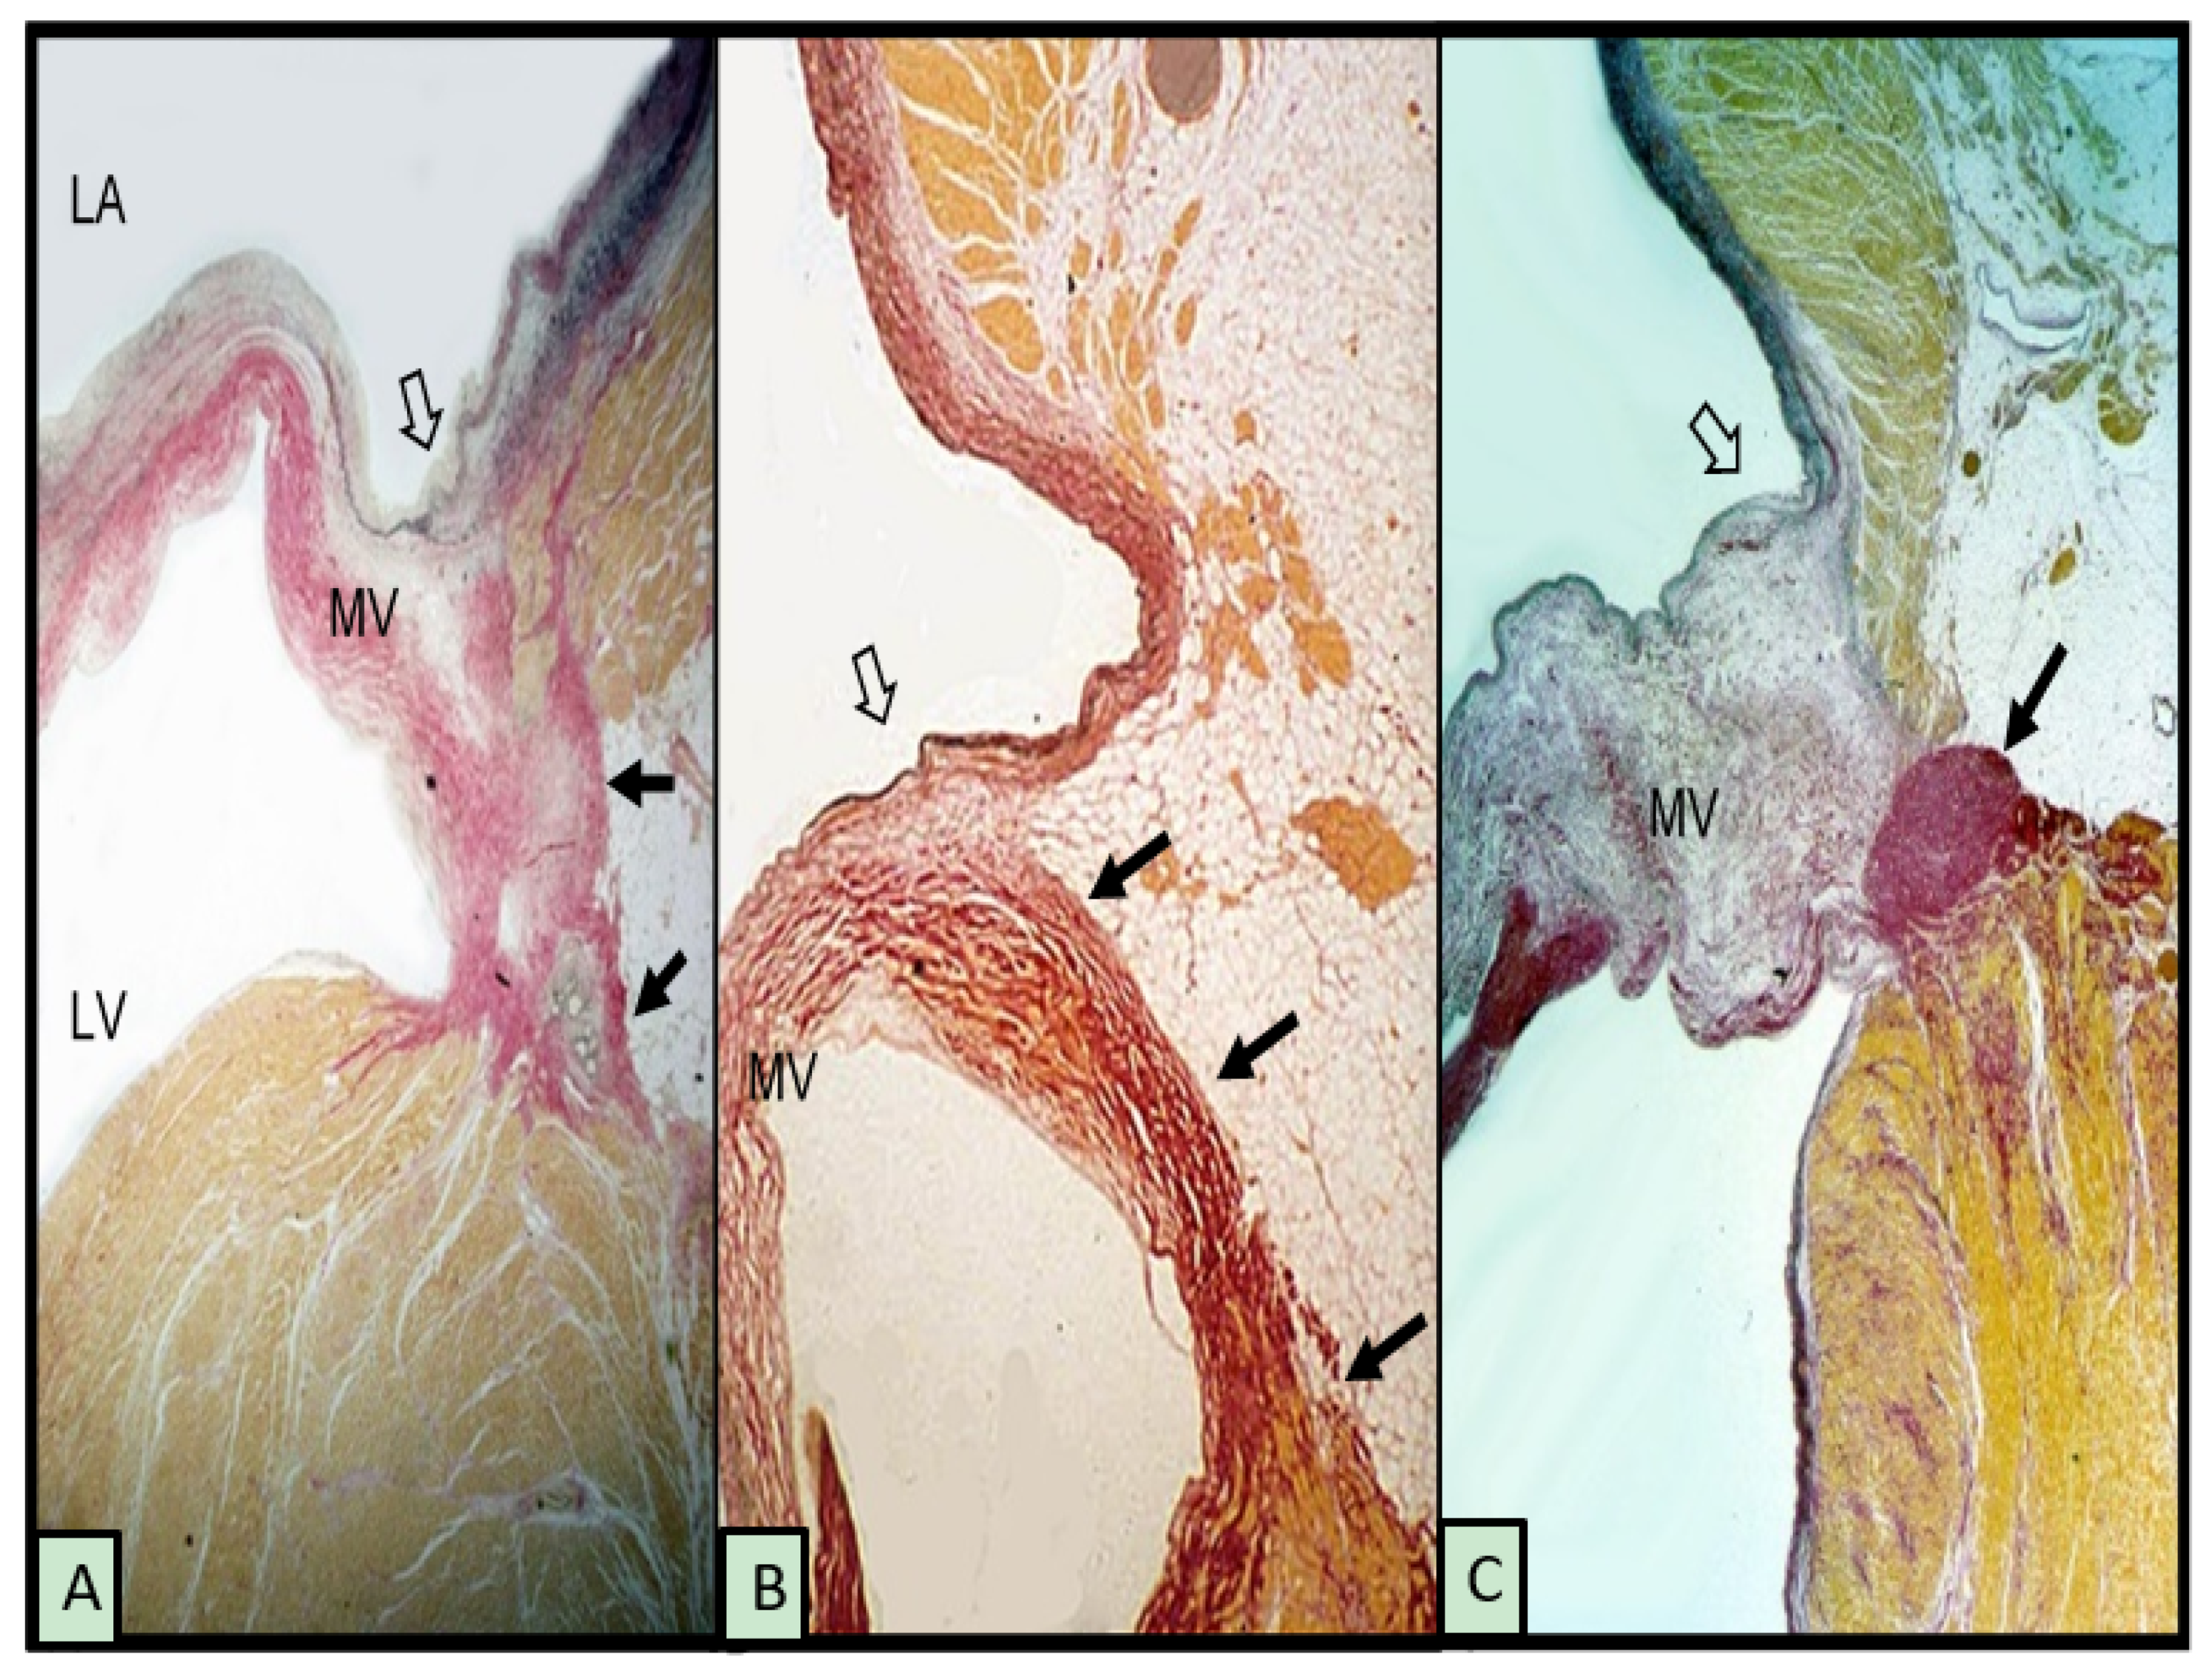

Although the term annulus implies a complete ring or fibrous cord-like structure around the mitral orifice that hinges the leaflet while separating the adjacent atrial and ventricular walls, this arrangement is uncommon. McAlpine [18] in 1975 asserted that the mitral annulus does not exist as a complete ring, although the term remains in use, as in this article, to refer to the attachment, or hinge line, of the leaflet at the atrioventricular junction. His dissections elegantly revealed a membrane-like structure more ventricular to the hinge line, which he termed the subvalvar segment of the aorto-ventricular membrane around the ostium of the LV. Indeed, subsequent anatomical and imaging studies have shown considerable variability in the attachment of the posterior leaflet at the hinge line [11,19,20]. When viewed on histological sections, instead of a discrete fibrous nodule representing a cord, often, there is a thin, fibrous membrane separating the atrial and ventricular walls. In some hearts, the leaflet is hinged to the atrial wall or the ventricular wall (Figure 1A,B). The gap between is filled with fibro-fatty tissues of the atrioventricular groove. In MAD associated with MMVD, there is a distinct separation conceivably, in part, also due to the thickness of the leaflet (Figure 1C).

Figure 1.

Histological sections from 3 hearts showing the posterior leaflet at the mitral hinge line (open arrows) and variations in mitral annular disjunction (small black arrows). (A,B) have normal leaflets. The myxomatous leaflet in (C) is hinged to the atrial wall and a cord-like annulus (arrow). The elastic van Gieson stain colors fibrous tissue red, myocardium yellow, and elastic dark blue or black. LV = left ventricle, LA = left atrium, and MV = mitral valve.